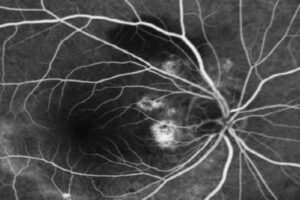

La vasculopathie polypoïdale choroïdienne (VPC) a été décrite pour la première fois par Yannuzzi en 1982. Elle est décrite comme une vascularisation anormale et ramifiée de la choroïdienne interne, associée…